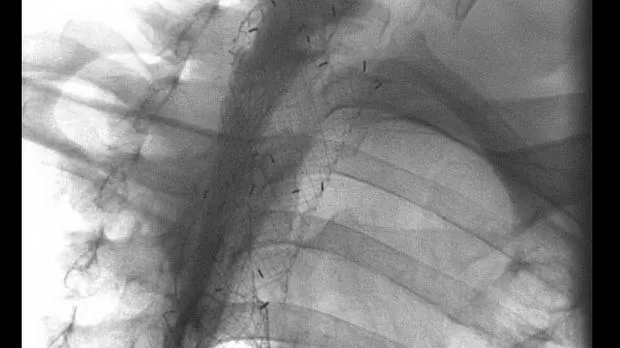

При выполнении фибробронхоскопии и вмешательства в обоих случаях отмечалось сдавление извне и деформация просвета трахеи до щелевидной формы, но удалось свободно провести аппарат ниже участка сужения. Стент устанавливался в зону сужения по тонкой струне-проводнику, которая заводилась в нижнедолевой бронх справа. Сразу после установки стента отмечалось улучшение состояния пациентов, а полное раскрытие стента происходило в течение 10-12 часов. При томографии трахеи через 12 часов после стентирования стент был полностью раскрыт.

Через 2 и 4 дня после установки стента в трахею им выполнена установка металлического саморасправляющегося стент длиной 12 см и диаметром 18 мм в пищевод. Устанавливались асимметричный и шеечный стенты, поскольку верхний край сужения располагался на 1 и 2 см ниже глоточно-пищеводного перехода. Установка проводилась под рентген-контролем с маркировкой участка сужения рентген-контрастными метками, которые приклеивались к коже. Осложнений не было. Прием пищи через рот восстановлен.